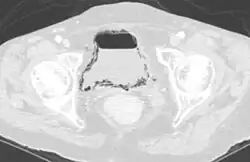

- Die emphysematöse Zystitis mit Gasbildung in der Blase und in der Blasenwand durch Bakterien oder Pilze ist eine seltene Erkrankung, die häufiger Diabetiker und Frauen betrifft.[18][19]